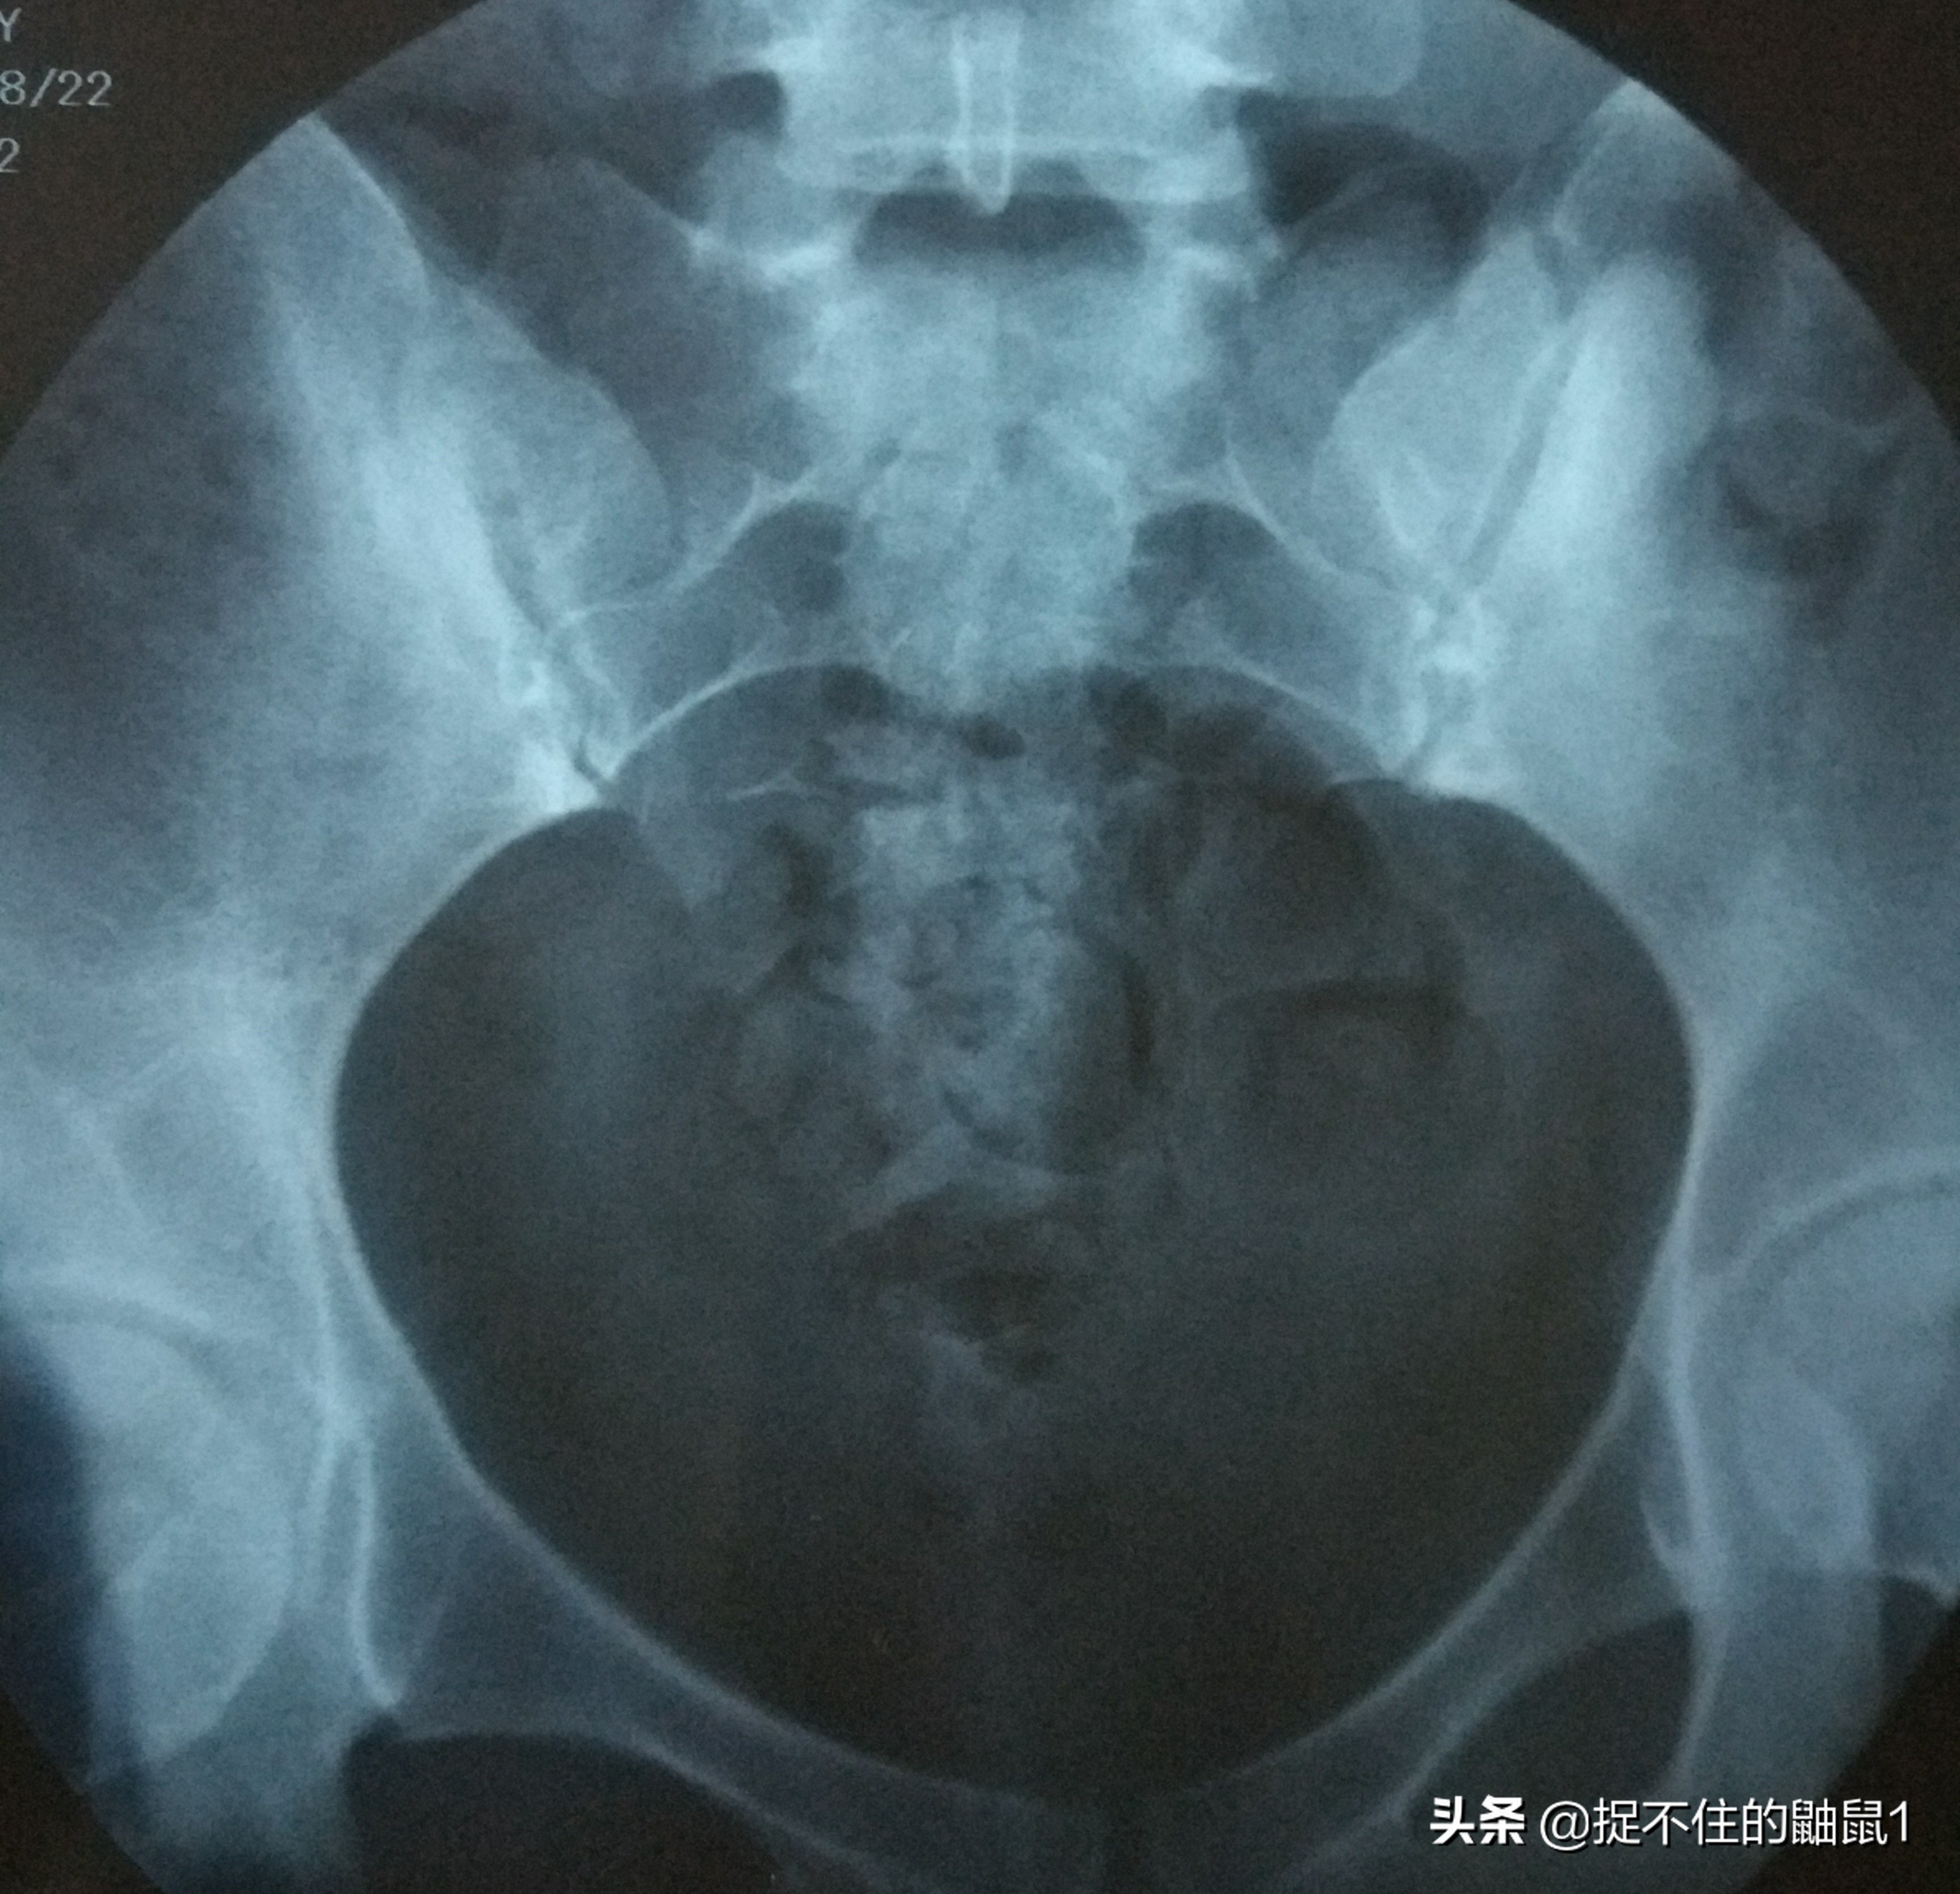

这是第二天碘油弥散后的造影,没弥散开,就是输卵管不通,这是医生跟我说的,我也看不懂